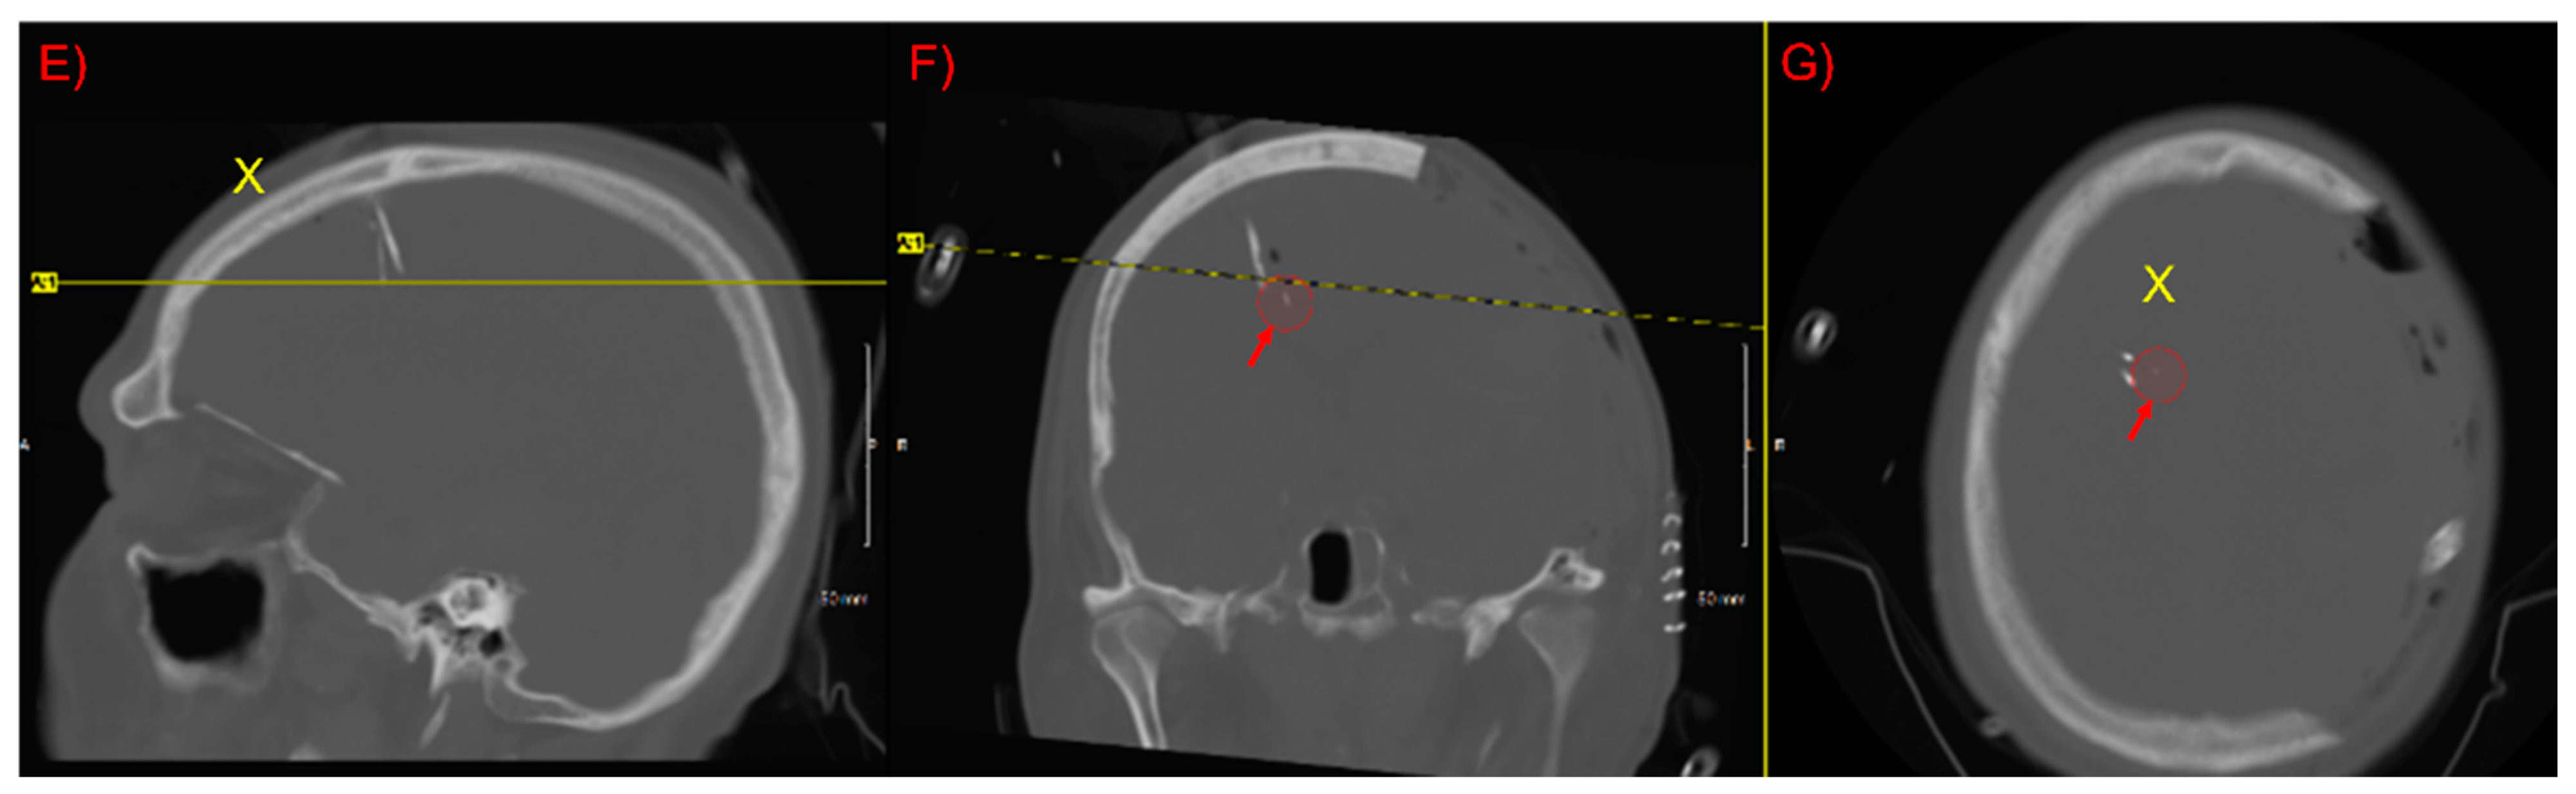

2.1. Study Design and Patient Details